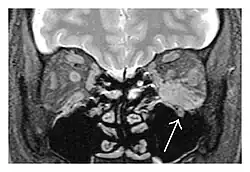

| Mass lesion around the right optic disc in a 44-year-old man with IgG4-related ophthalmic disease and a serum IgG4 of 599 mg/dL.[1] (T2-weighted MRI) | |

The extent of inflammation that can occur in IgG4-ROD is well demonstrated on magnetic resonance imaging (MRI).